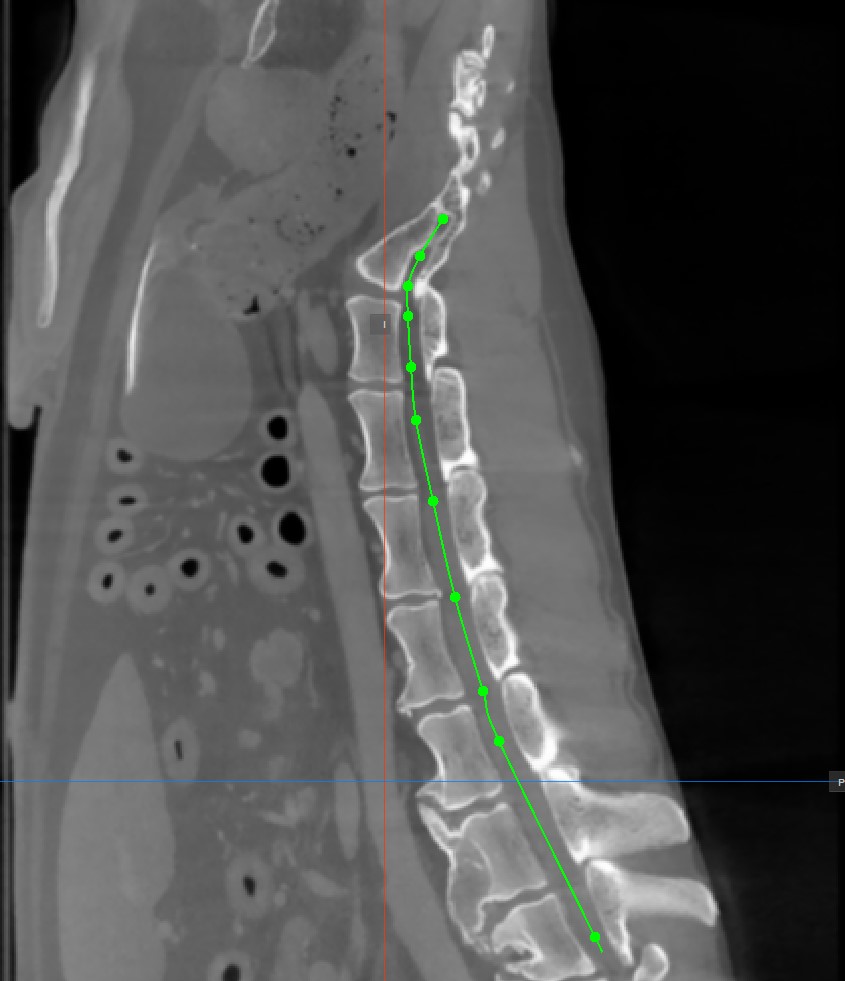

Curved MPR (CMPR) View

Curved MPR, a variation of MPR, creates cross-sectional images along a user-drawn curved path. CMPR can be especially useful when visualizing complex or irregular structures, such as blood vessels or various spinal structures.

The curved MPR straightened view, along with its associated slicers are located on the left side of the viewer, while the standard MPR in all three available planes is located on the right side of the window.